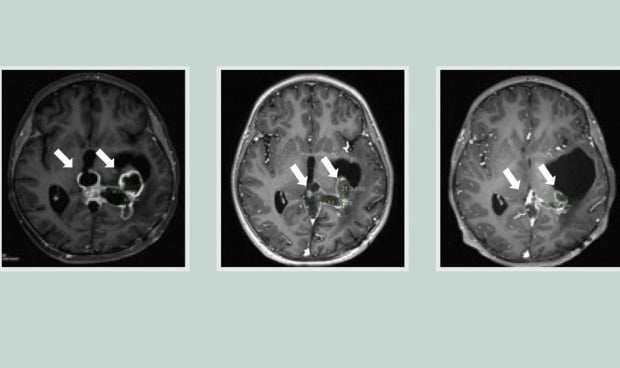

En dos ensayos clínicos en los que se probó el compuesto ONC201 en un total de 71 pacientes con gliomas difusos de la línea media mutados con H3K27M, la mediana de supervivencia global fue de casi 22 meses para los tumores que no habían recidivado en el momento de la inscripción. Casi un tercio de los pacientes vivió más de dos años.

Mientras tanto, Koschmann y su coautor, Sriram Venneti, intentaban averiguar qué ocurría en estas células tumorales. Durante el ensayo, recogieron líquido cefalorraquídeo de los pacientes. Utilizaron este líquido para analizar los cambios metabólicos y descubrieron que el ONC201 penetraba en las células tumorales y afectaba a las mitocondrias. Los pacientes que respondieron al fármaco presentaron un aumento de un metabolito llamado L-2HG producido por las células tumorales.

Koschmann califica el hallazgo de "muy inesperado". El equipo descubrió que el aumento de L-2HG invertía las señales epigenéticas definitorias del tumor, lo que hacía que las células tumorales se diferenciaran más y se dividieran menos. Cuanto más tiempo recibían ONC201 los pacientes, más tumores presentaban estas inversiones epigenéticas.